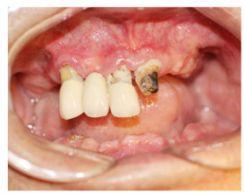

種牙前照片

通過X光片可以看到,醫(yī)生雖然盡量設(shè)計(jì)連冠種植,但還是用了十七個(gè)植體,盡管已經(jīng)是多次調(diào)整后的精簡(jiǎn)方案,但手術(shù)時(shí)長(zhǎng)依然長(zhǎng)達(dá)一天。位老先生之前在另一家醫(yī)院咨詢時(shí),醫(yī)生給的方案是種二十二個(gè)植體,光是種植費(fèi)用就令人大呼“害怕”了。